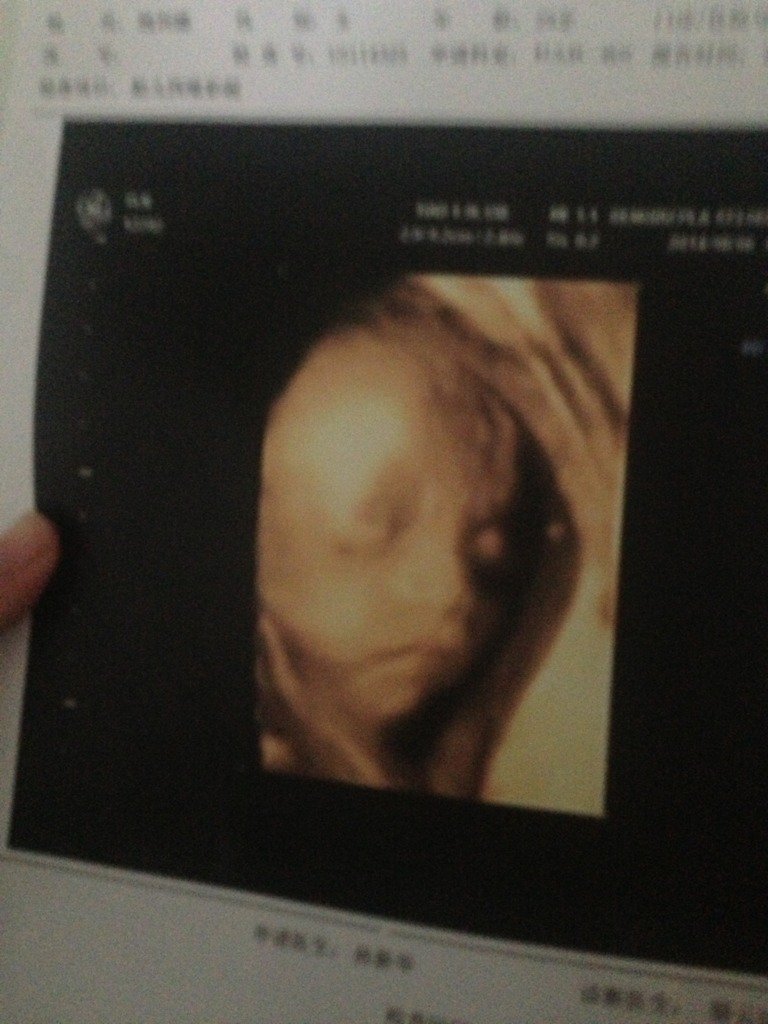

今天刚做的四维彩超真的好激动啊,很清楚的看到宝宝在肚子里的样子了,大家帮我看看像男孩女孩 今天刚做的四维彩超真的好激动啊,很清楚的看到宝宝在肚子里的样子了,大家帮我看看像男孩女孩 点击展开 娜、些年华 2014-10-16 22:19 为您推荐: 其他回答 男女都一样只要健康 罗可芯 2014-10-16 22:36 不客气!!! 爱宝宝521 2014-10-16 22:26 好像是女儿哟 小七_9wax 2014-10-16 22:23 嗯嗯那就是男孩,祝宝妈和宝宝健康平安快乐幸福哦 爱宝宝521 2014-10-16 22:23 女孩,,,,, 阳光女孩_sqiu 2014-10-16 22:23 加载更多 相关问题 今天刚做的四维彩超,医生说一切正常,终于放心了 大家给看看是男孩女孩… 怀孕26周 今天做四维彩超发育都很好,宝宝是趴在肚子里的没有看清脸,小手 肝肾脚 小屁股 大脑 我肚子上的黑线是不是很浅,帮我看看男孩女孩